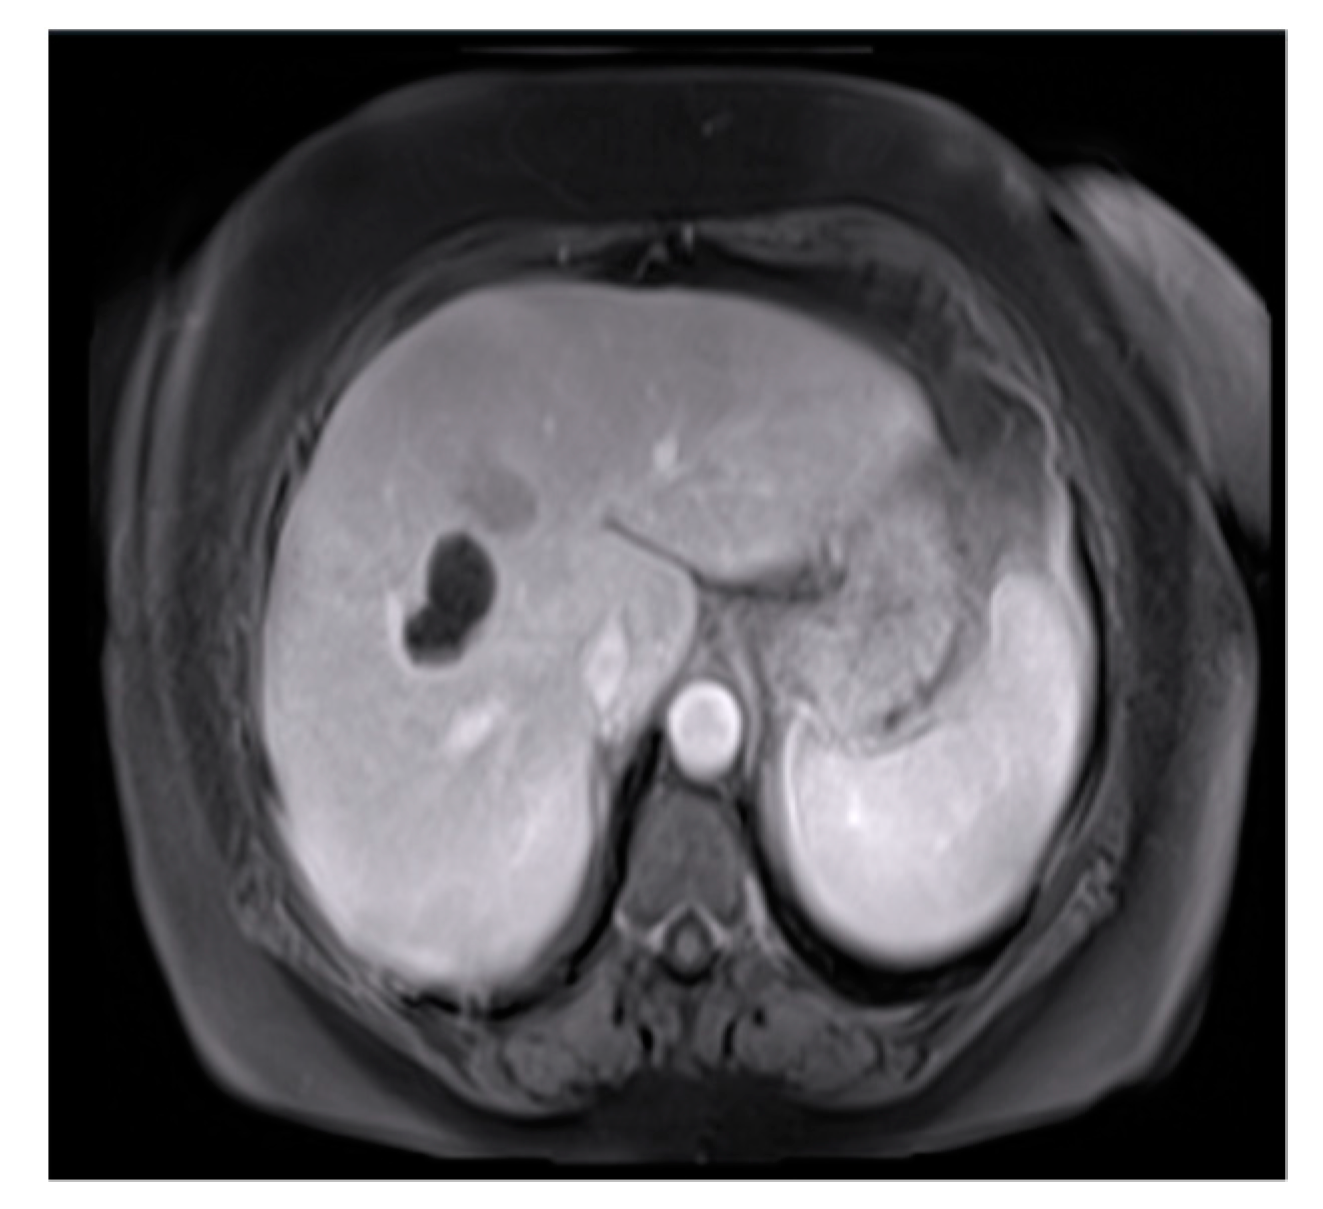

The dataset utilized in this study was the cancer genome atlas liver hepatocellular carcinoma (TCGA-LIHC) data [4]. We related cancer phenotypes to genotypes by providing clinical images of TCGA [5]. Clinical, genetic, and pathological data were obtained from the Genomic Data Commons (GDC) data portal, while the radiological data were collected from TCIA. The original image size was 256 × 256 pixels and extracted to conduct preliminary testing and analysis (Figure 3). Figure 3 showcases the practical application of the processing techniques on the dataset [6].

Figure 3.

Original image.